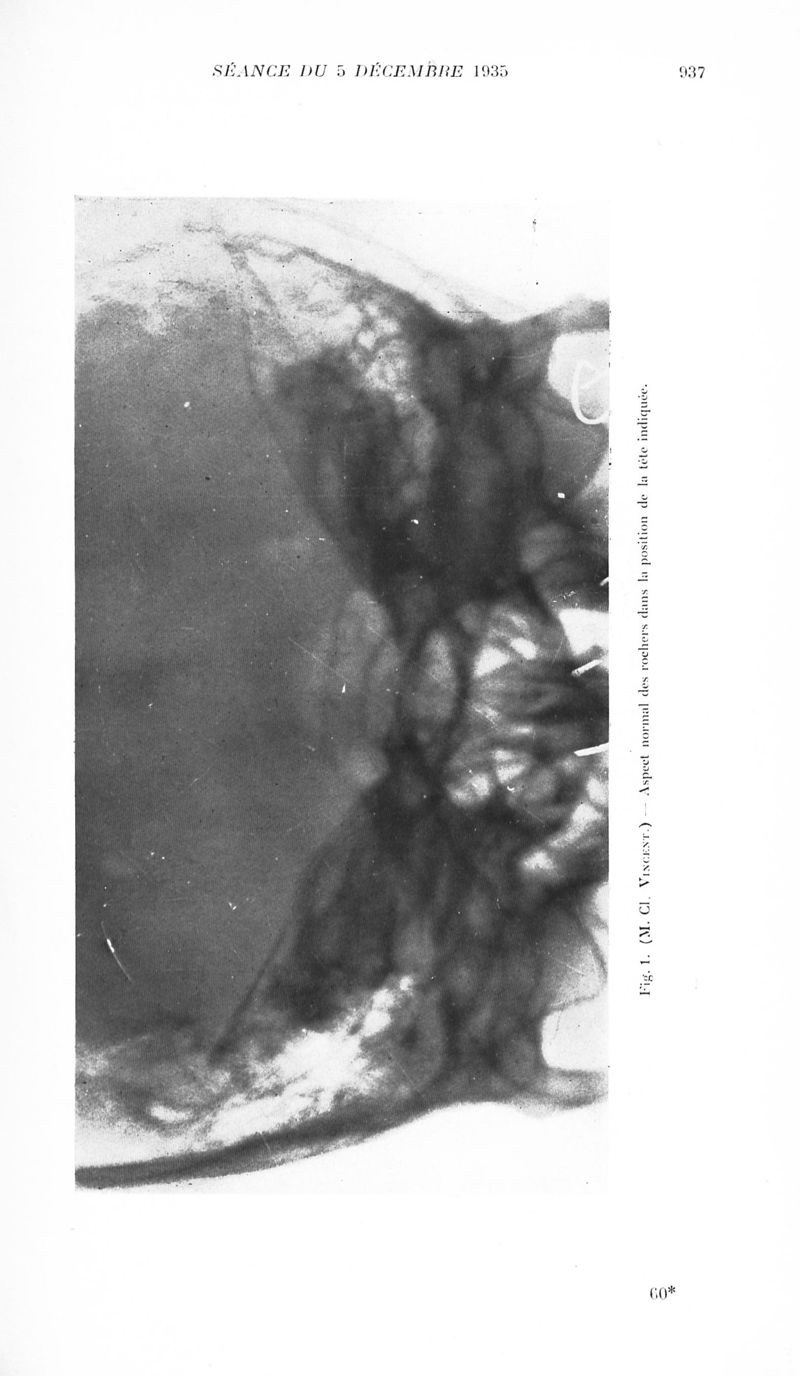

Revue neurologique

1935, vol 2. - Paris : Masson , 1935.